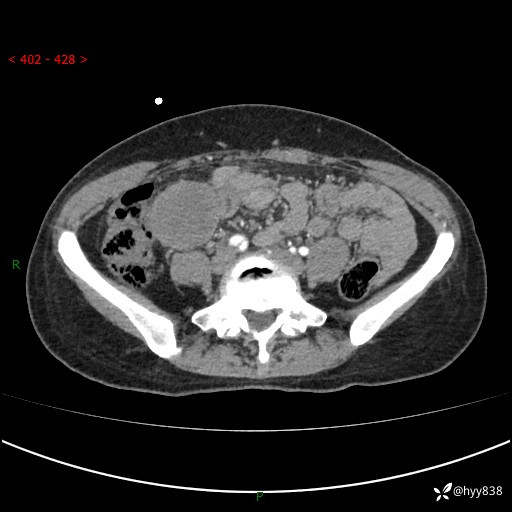

年轻女性,发现腹腔肿物1周。圆圆的肿物,诊断有难度---结果公布~

现病史:患者自诉于1周前无明显诱因出现剑突下间断性隐痛,尚可忍受,不向其它部位放射,无恶心呕吐、腹泻便秘等不适,于当地市第二人民医院就诊,行CT结果示:1.右中腹占位,间叶组织来源可能2.小肠梗阻3.盆腔积液4.腹腔积液5.副脾6.肝囊肿;于荆州二医行抗炎,抑酸,护胃,补液等对症支持治疗;患者病情好转,今为求进一步诊治,遂来我院门诊就诊,门诊以“腹腔肿瘤”收入院。 起病以来,患者精神、睡眠、饮食一般,大小便正常,近期体力体重无明显改变。

腹部CT增强(外院平扫)